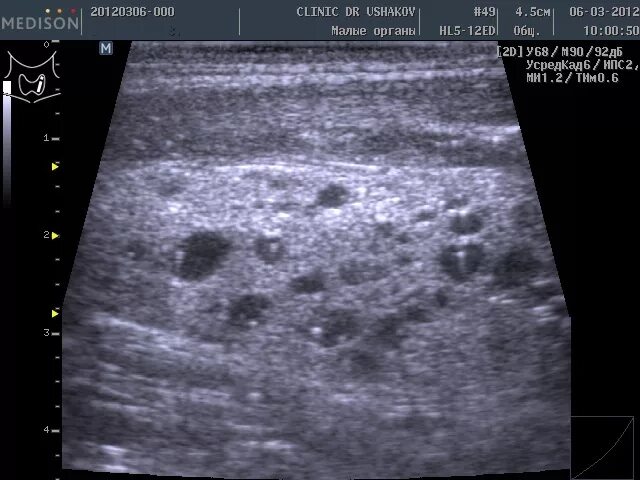

Диффузные л